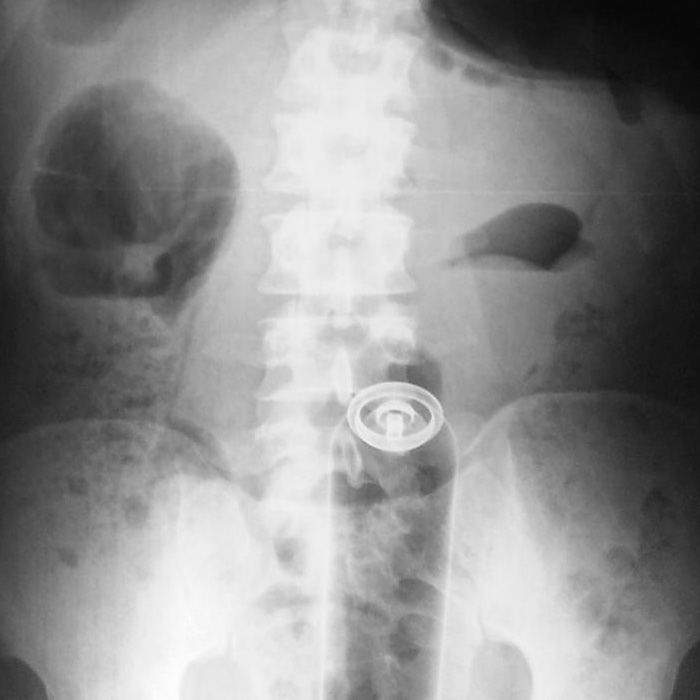

▼這個就是身體裡塞個一個罐子

圖片來自:ems1